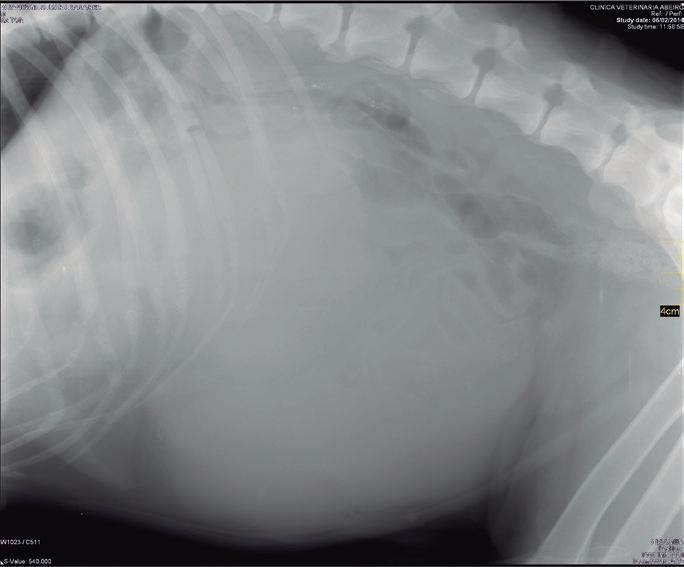

Maine Coon, hembra castrada de 8 años, 3,5 kg y condición corporal 5/9, diagnosticada mediante resonancia magnética de una lesión extradural que afectaba a los lóbulos parietal, temporal y occipital (posiblemente meningioma) y que le producía un cuadro de circling, que en el momento de la anestesia estaba controlado gracias al tratamiento con dexametasona 0,15 mg/ kg/24 h. Como otros antecedentes clínicos, la paciente presentaba barro biliar, iniciándose el tratamiento con ácido ursodesoxicólico.

Se presenta el caso de una gata sometida a craneotomía supratemporal para exéresis de un menigioma, en la que se realizó un mantenimiento anestésico intravenoso para mantener una mayor estabilidad hemodinámica durante la cirugía.